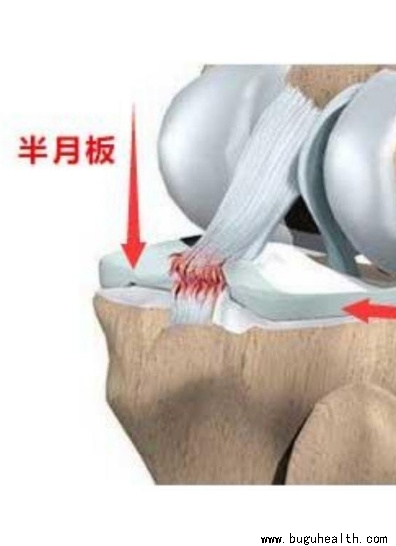

- 半月板是膝关节内胫骨和股骨间隙内的纤维性板状软骨组织,外观呈“C”型,故称为半月板。位于膝关节内侧的叫做内侧半月板,类似“C”型,外侧的叫做外侧半月板,类似“O”型。其中内侧半月板与关节囊周边连接紧密,活动性差。外侧半月板后角存在腘肌腱裂隙,活动度略大。半月板在关节内伴随膝关节一起运动,可以起到缓冲.....

- 半月板是膝关节里面的一对软骨组织。大家知道,膝关节连接着股骨和胫骨,但是股骨下端是两个圆球,胫骨上端是两个平台,如果它们直接碰面的话,接触的是两个点,这样产生的压强会很大,软骨会很快被磨损,并且贴合的稳定性会很差。而环形的半月板就是两者之间的媒介,让股骨和胫骨的接触面变大,并且贴合变得紧密而稳定。打.....